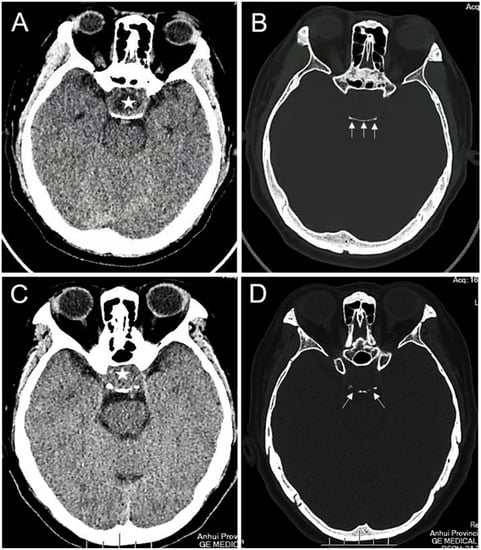

Altogether, 178 eligible patients with PAs were included in this study and were divided into the Ki-67 < 3% cohort (n = 72) and the Ki-67 ≥ 3% cohort (n = 106). The specific characteristics of the two cohorts are presented in Table 1. Among them, 86 (48.31%) patients were men, and 92 (51.69%) were women, Overall, the mean age of all the patients was 53.08 ± 12.22 years. Of the 178 patients, 44 (24.72%) patients had a Knosp grade ≥ 3, and the tumor broke through the sellar floor in 20 (11.24%) cases. Overall, 111 (62.36%) tumors presented a rich blood supply (Figure 1), and 112 (62.92%) cases indicated erosion of the dorsum sellae bone (Figure 2).

Figure 2. The erosion of the dorsum sellae bone: (A,B) intrasellar PA (asterisk) with an enlarged sella and an intact dorsum sellae bone (white arrows); (C,D) Intrasellar PA (asterisk) with an enlarged sella and erosion of the dorsum sellae bone (white arrows).

The pituitary fossa accommodates the pituitary gland, bounded anteriorly by the tuberculum sellae and posteriorly by the dorsum sellae. Lesions in the pituitary fossa often leads to erosion and thinning of the dorsum sellae bone [25]. Interestingly, PAs in the sellar region can cause destruction of the dorsum sellae bone [26]. In our study, 77.36% of PAs with a Ki-67 index ≥ 3% had erosion of the dorsum sellae bone, which was significantly higher than that of the Ki-67 index < 3% group (41.67%). We hypothesized that this was due to the absorption and destruction of the dorsum sellae bone by tumor cells with a high Ki-67 index during rapid proliferation. This also suggested that the occurrence of dorsum sellae bone erosion was significantly correlated with a high Ki-67 index, and further analysis revealed that erosion of the dorsum sellae bone was an independent factor of the Ki-67 index. Here, the Knosp grade were not correlated with the Ki-67 index, which is consistent with previous studies [12,22].